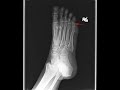

This patient presented with acute onset foot pain. Radiographs of the foot were obtained which demonstrates a lytic, expansile lesion in the proximal phalanx of the small toe. Additionally, there is a superimposed cortical disruption of the proximal phalanx as indicated by the red arrow secondary to pathologic fracture. On close inspection, there are a couple small foci of calcification within the lesion consistent with a chondroid matrix. The imaging features of this lesion are most consistent with an enchondroma with pathologic fracture. Enchondromas are benign cartilaginous tumors which often occur in the hands and foot. Even without pathologic fracture, they may be cause of pain in an extremity.